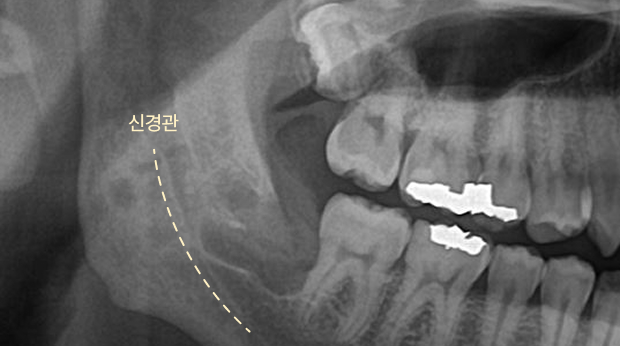

매복 사랑니 발치

고난도 수술 진료

임플란트와 사랑니 발치는 외과적 시술로 잇몸을 절개하는 외과적 시술은

짧으면 짧을 수록 시술 후 붓기와 통증이 최소화됩니다.

치과의사 경력 14년차 구강외과 전문의가 빠르고 안전하게, 아프지 않게 수술해 드립니다.

치과경력 14년차 구강외과 전문의